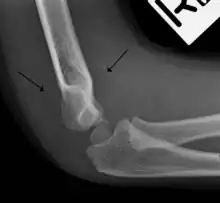

A normal anterior fat pad in a non-fractured arm.

Anterior sail signs as well as posterior fat pad in a child with a supracondylar fracture.